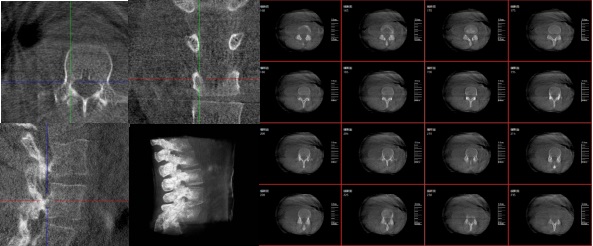

三維重建技術(shù)影像